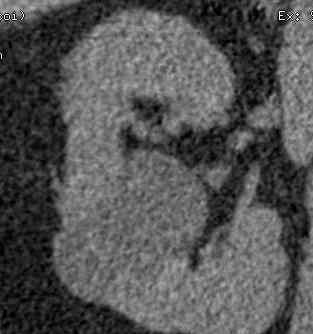

如上图,体检b超显示肾积水,CT尿路造影。左图,平扫后重建显示(右)肾囊肿突入肾盂。右图,静脉注射造影剂后经过一定时间延迟,输尿管起始处(右侧)造影剂填充良好,肾盂内囊肿内无造影剂填充。